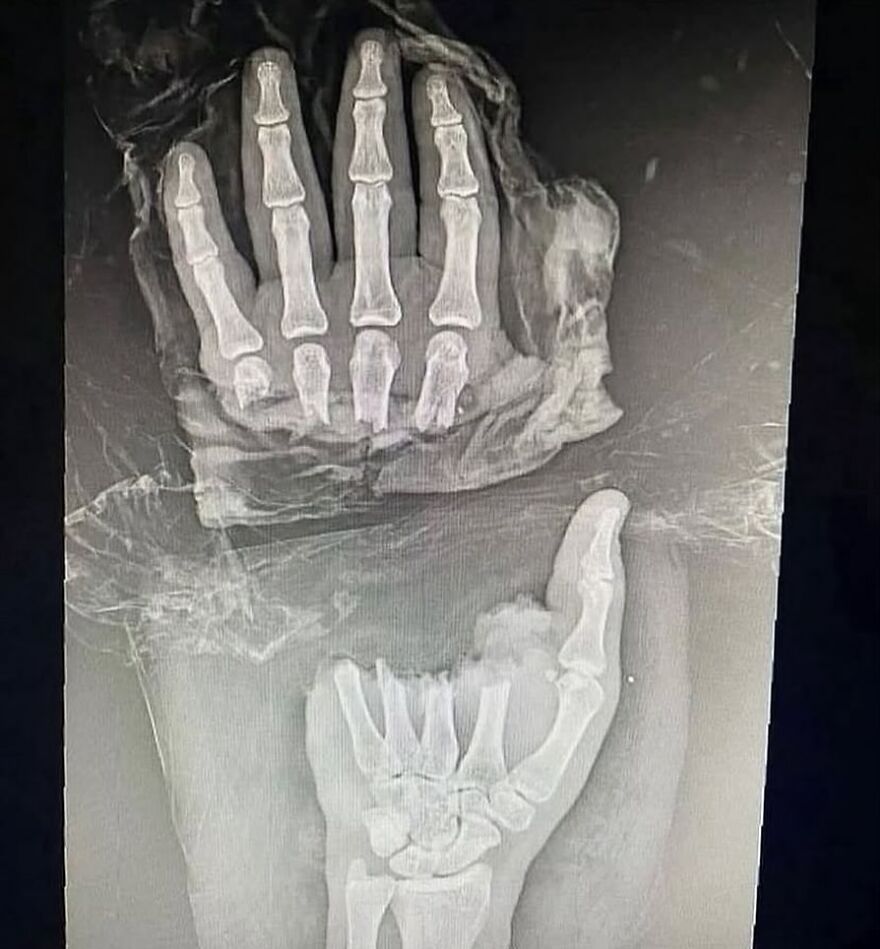

Plain radiograph of wrist joint shows polydactyly with duplication of ulna, duplication of ulnar side of carpal bones, metacarpals and phalanges, absence of radius and absence of thumb. Eight triphalangeal digits are seen. The middle phalanx of medial index finger is hypoplastic